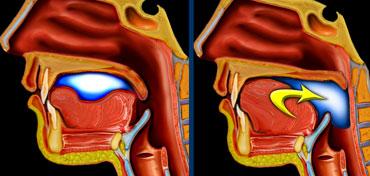

TRÁI: Giai đoạn miệng hay giai đoạn chuẩn bị. PHẢI: Vận chuyển đến hầu họng và kích hoạt phản xạ nuốt thực sự.

Giai đoạn miệng

Trong giai đoạn miệng, thức ăn được chuẩn bị để nuốt và sau đó được vận chuyển đến hầu họng.

Đây là giai đoạn chuẩn bị, trong đó thức ăn được giữ trong miệng trong khi nền lưỡi và vòm miệng mềm đóng khoang miệng ở phía sau để ngăn thức ăn tràn vào thanh quản và khí quản đang mở.

Một viên thức ăn (bolus) được hình thành ở phần trung tâm của lưỡi, sau đó được đẩy ra phía sau về phía hầu họng nhờ động tác nâng lưỡi từ trước ra sau.

Khi bolus đi vào hầu họng, phản xạ nuốt thực sự hay phản xạ hầu họng được kích hoạt.

Sự nâng lên của vòm miệng mềm ngăn không cho thức ăn đi vào khoang mũi.

Tiếp theo, các cơ khít hầu co lại đẩy bolus sâu hơn vào hầu họng, hướng về phía cơ thắt nhẫn hầu.

Thanh quản ngăn thức ăn đi vào khí quản bằng cách lần lượt đóng dây thanh âm thật, nếp thanh âm giả và các nếp phễu-thanh thiệt.

Sự co thắt của cơ khít hầu dưới tiếp theo là sự giãn của cơ nhẫn hầu, cho phép bolus đi vào thực quản.